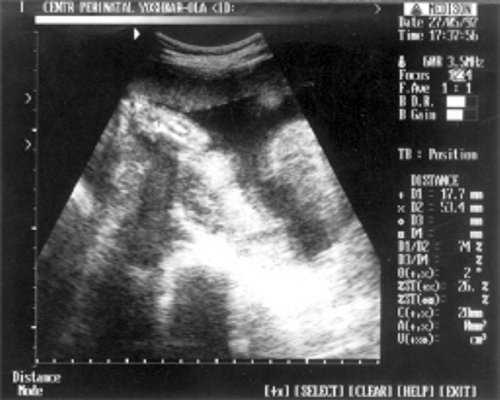

Кости предплечья = 17,5 мм - 15,5 нед. (рис. 4)

- Кости предплечья = 17,5 мм - 15,5 нед. (рис. 4)

Рис. 4. УЗИ плода - кости предплечья.